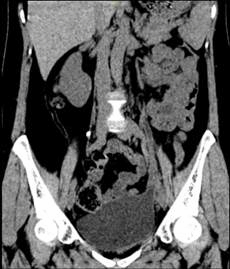

图三、四 术后3月泌尿系三维CT

在麻醉科和手术室的密切配合下,王春阳教授团队历时4小时,成功用6cm膀胱肌瓣替代了损伤的输尿管、留置输尿管支架完成手术。术中出血量仅20mL,术后连续观察三天没有再发生漏尿情况,患者顺利出院,出院3个月后引流管顺利拔除,仍无漏尿再发,治疗效果受到患者及家属高度认可。